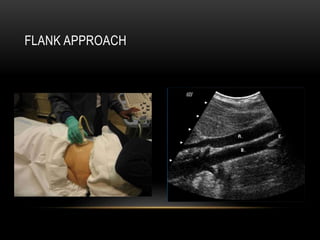

Roll the patient into a decubitus position to avoid bowel gas and improve

visibility of the renal artery, especially the mid to distal portion.

FLANK APPROACH